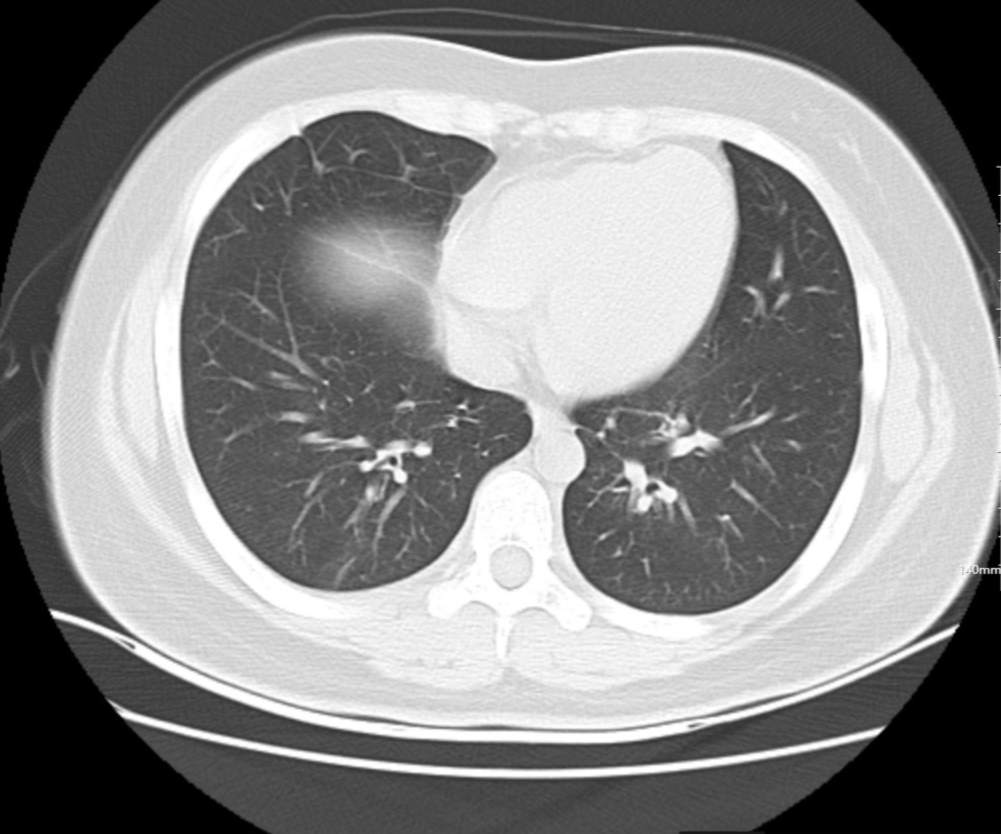

肺部CT:

支气管血管束增粗且伴 < 2 个肺叶的磨玻璃密度影, 多提示为单纯性百日咳肺炎。(下图:支气管血管束增粗, 两肺下叶基底段少许磨玻璃密度影)

如出现肺内支气管血管束增粗, 伴≥3 个肺叶斑片影、亚段性实变及支气管气象时, 提示患儿病情较重,可能合并其他感染。

患者2天前出现阵发性咳嗽,咳绿脓痰,伴发热,体温最高达37.8℃(耳),偶有胸痛,无呼吸困难,无咯血盗汗,无寒战、惊厥,来我院门诊查胸部CT“两下肺模糊斑片影”,诊断为“肺炎”。